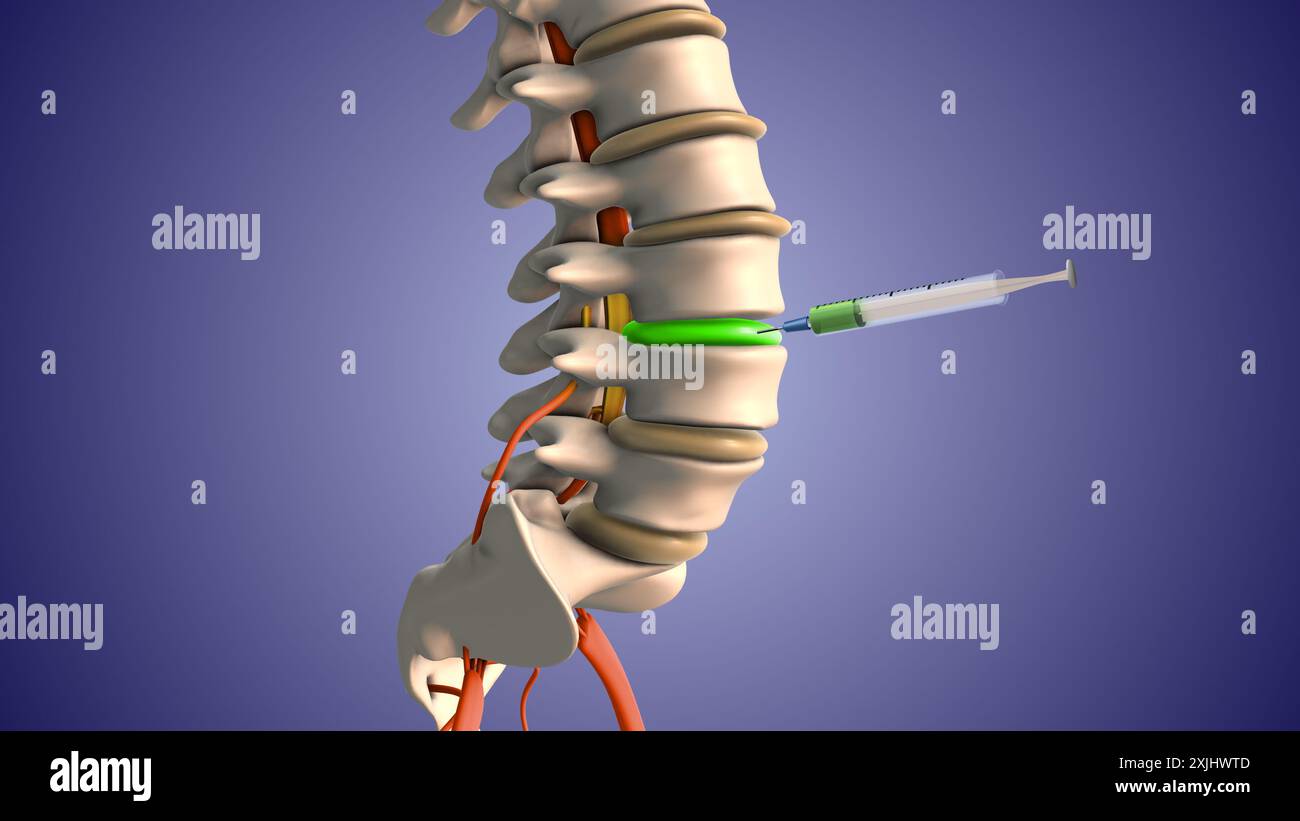

Injektion von Steroiden zur Behandlung von Bandscheibenvorfällen Stockfotohttps://www.alamy.de/image-license-details/?v=1https://www.alamy.de/injektion-von-steroiden-zur-behandlung-von-bandscheibenvorfallen-image613820155.html

Injektion von Steroiden zur Behandlung von Bandscheibenvorfällen Stockfotohttps://www.alamy.de/image-license-details/?v=1https://www.alamy.de/injektion-von-steroiden-zur-behandlung-von-bandscheibenvorfallen-image613820155.htmlRF2XJHWTB–Injektion von Steroiden zur Behandlung von Bandscheibenvorfällen

Injektion von Steroiden zur Behandlung von Bandscheibenvorfällen Stockfotohttps://www.alamy.de/image-license-details/?v=1https://www.alamy.de/injektion-von-steroiden-zur-behandlung-von-bandscheibenvorfallen-image613820158.html

Injektion von Steroiden zur Behandlung von Bandscheibenvorfällen Stockfotohttps://www.alamy.de/image-license-details/?v=1https://www.alamy.de/injektion-von-steroiden-zur-behandlung-von-bandscheibenvorfallen-image613820158.htmlRF2XJHWTE–Injektion von Steroiden zur Behandlung von Bandscheibenvorfällen

Injektion von Steroiden zur Behandlung von Bandscheibenvorfällen Stockfotohttps://www.alamy.de/image-license-details/?v=1https://www.alamy.de/injektion-von-steroiden-zur-behandlung-von-bandscheibenvorfallen-image613820156.html

Injektion von Steroiden zur Behandlung von Bandscheibenvorfällen Stockfotohttps://www.alamy.de/image-license-details/?v=1https://www.alamy.de/injektion-von-steroiden-zur-behandlung-von-bandscheibenvorfallen-image613820156.htmlRF2XJHWTC–Injektion von Steroiden zur Behandlung von Bandscheibenvorfällen

Injektion von Steroiden zur Behandlung von Bandscheibenvorfällen Stockfotohttps://www.alamy.de/image-license-details/?v=1https://www.alamy.de/injektion-von-steroiden-zur-behandlung-von-bandscheibenvorfallen-image613820157.html

Injektion von Steroiden zur Behandlung von Bandscheibenvorfällen Stockfotohttps://www.alamy.de/image-license-details/?v=1https://www.alamy.de/injektion-von-steroiden-zur-behandlung-von-bandscheibenvorfallen-image613820157.htmlRF2XJHWTD–Injektion von Steroiden zur Behandlung von Bandscheibenvorfällen